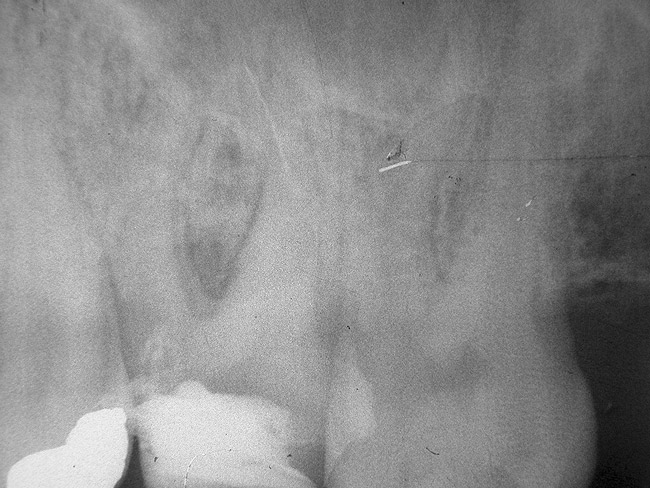

Figure 5a  Tooth No. 30 The preoperative radiograph revealed a periapical radiolucency and transported canals in the mesial root.

Figure 5a

Figure 5b  This procedural error may have delayed the progress of therapy or even made it impossible to thoroughly clean and shape the canal terminus. Root-end surgery was performed to enucleate the periapical pathology and debride previously uncleaned parts of the canals. On the apically resected root surface, an uncleaned portion of 1 canal and an isthmus connecting the 2 main canals became visible under high magnification (Figure 5B), which were prepared to 1 retrocavity using ultrasonic tips (Figure 5C) and filled with MTA (Figure 5D).

Figure 5b